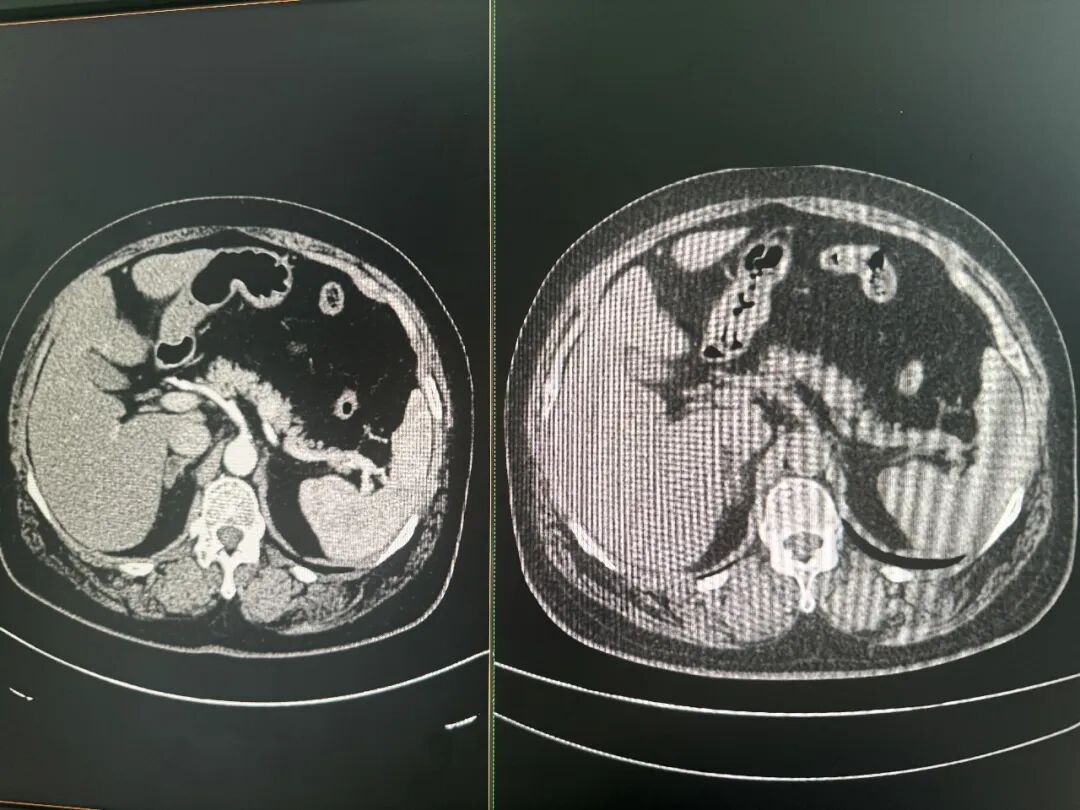

增强CT(左)和平扫CT(右)对比图 图片来源:每经记者 郑雨航 摄 达摩院医疗AI肿瘤早筛和影像智能的算法负责人张灵对每经记者解释,CT影像本质上是一串从-1024到1024的连续数值,不同数值对应不同密度的组织。许多细节超出了人眼的分辨极限,但理论上可以通过数据和算法进行分辨。